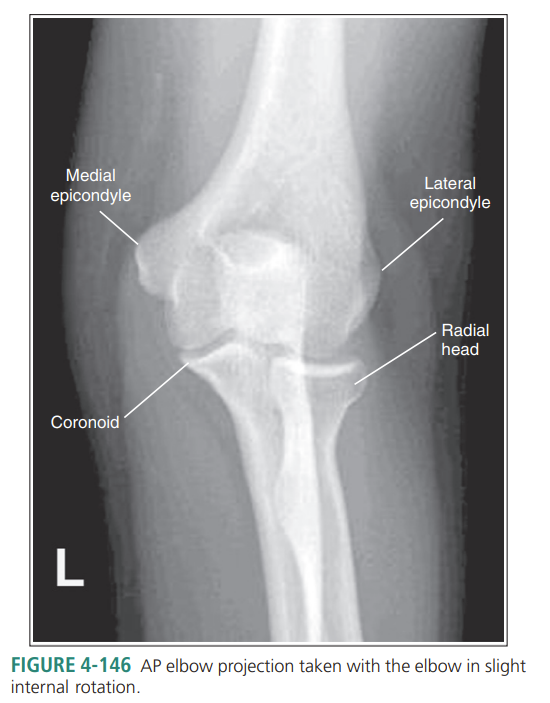

Elbow externally rotated and wrist internally rotated

Elbow internally rotated

More than 1/8 of the radial head is superimposing with the ulna

Internal rotation

Less than 1/8 of the radial head is superimposing with the ulna

External rotation

What is wrong with this external oblique elbow?

Obliquity is less than 45 degrees, meaning its under-rotated

Radius and ulna are not superimposed, but coronoid can be seen

Over-rotation with obliquity of more than 45 degrees

the distal capitulum surface is demonstrated too far distal to the distal surface of the medial trochlea and the radial head is placed too far posteriorly to the coronoid process

Proximal humerus is elevated

Distal capitulum is too far proximal to the distal medial trochlear surface of the radial head is too far anterior to the coronoid process

Distal forearm is depressed